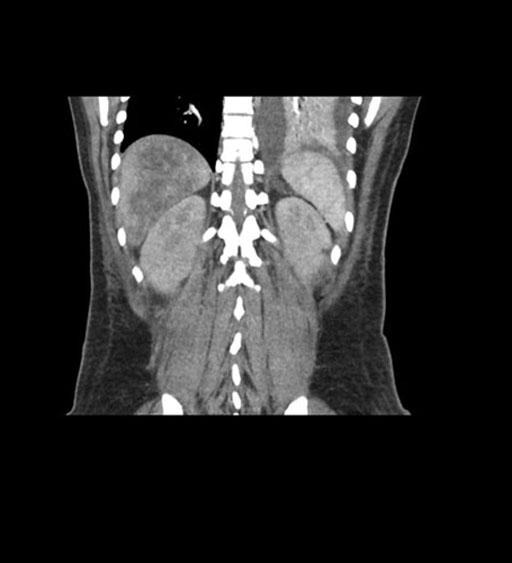

Coronal Arterial

Imaging analysis

Based on initial findings, which issue(s) would you be most concerned about?